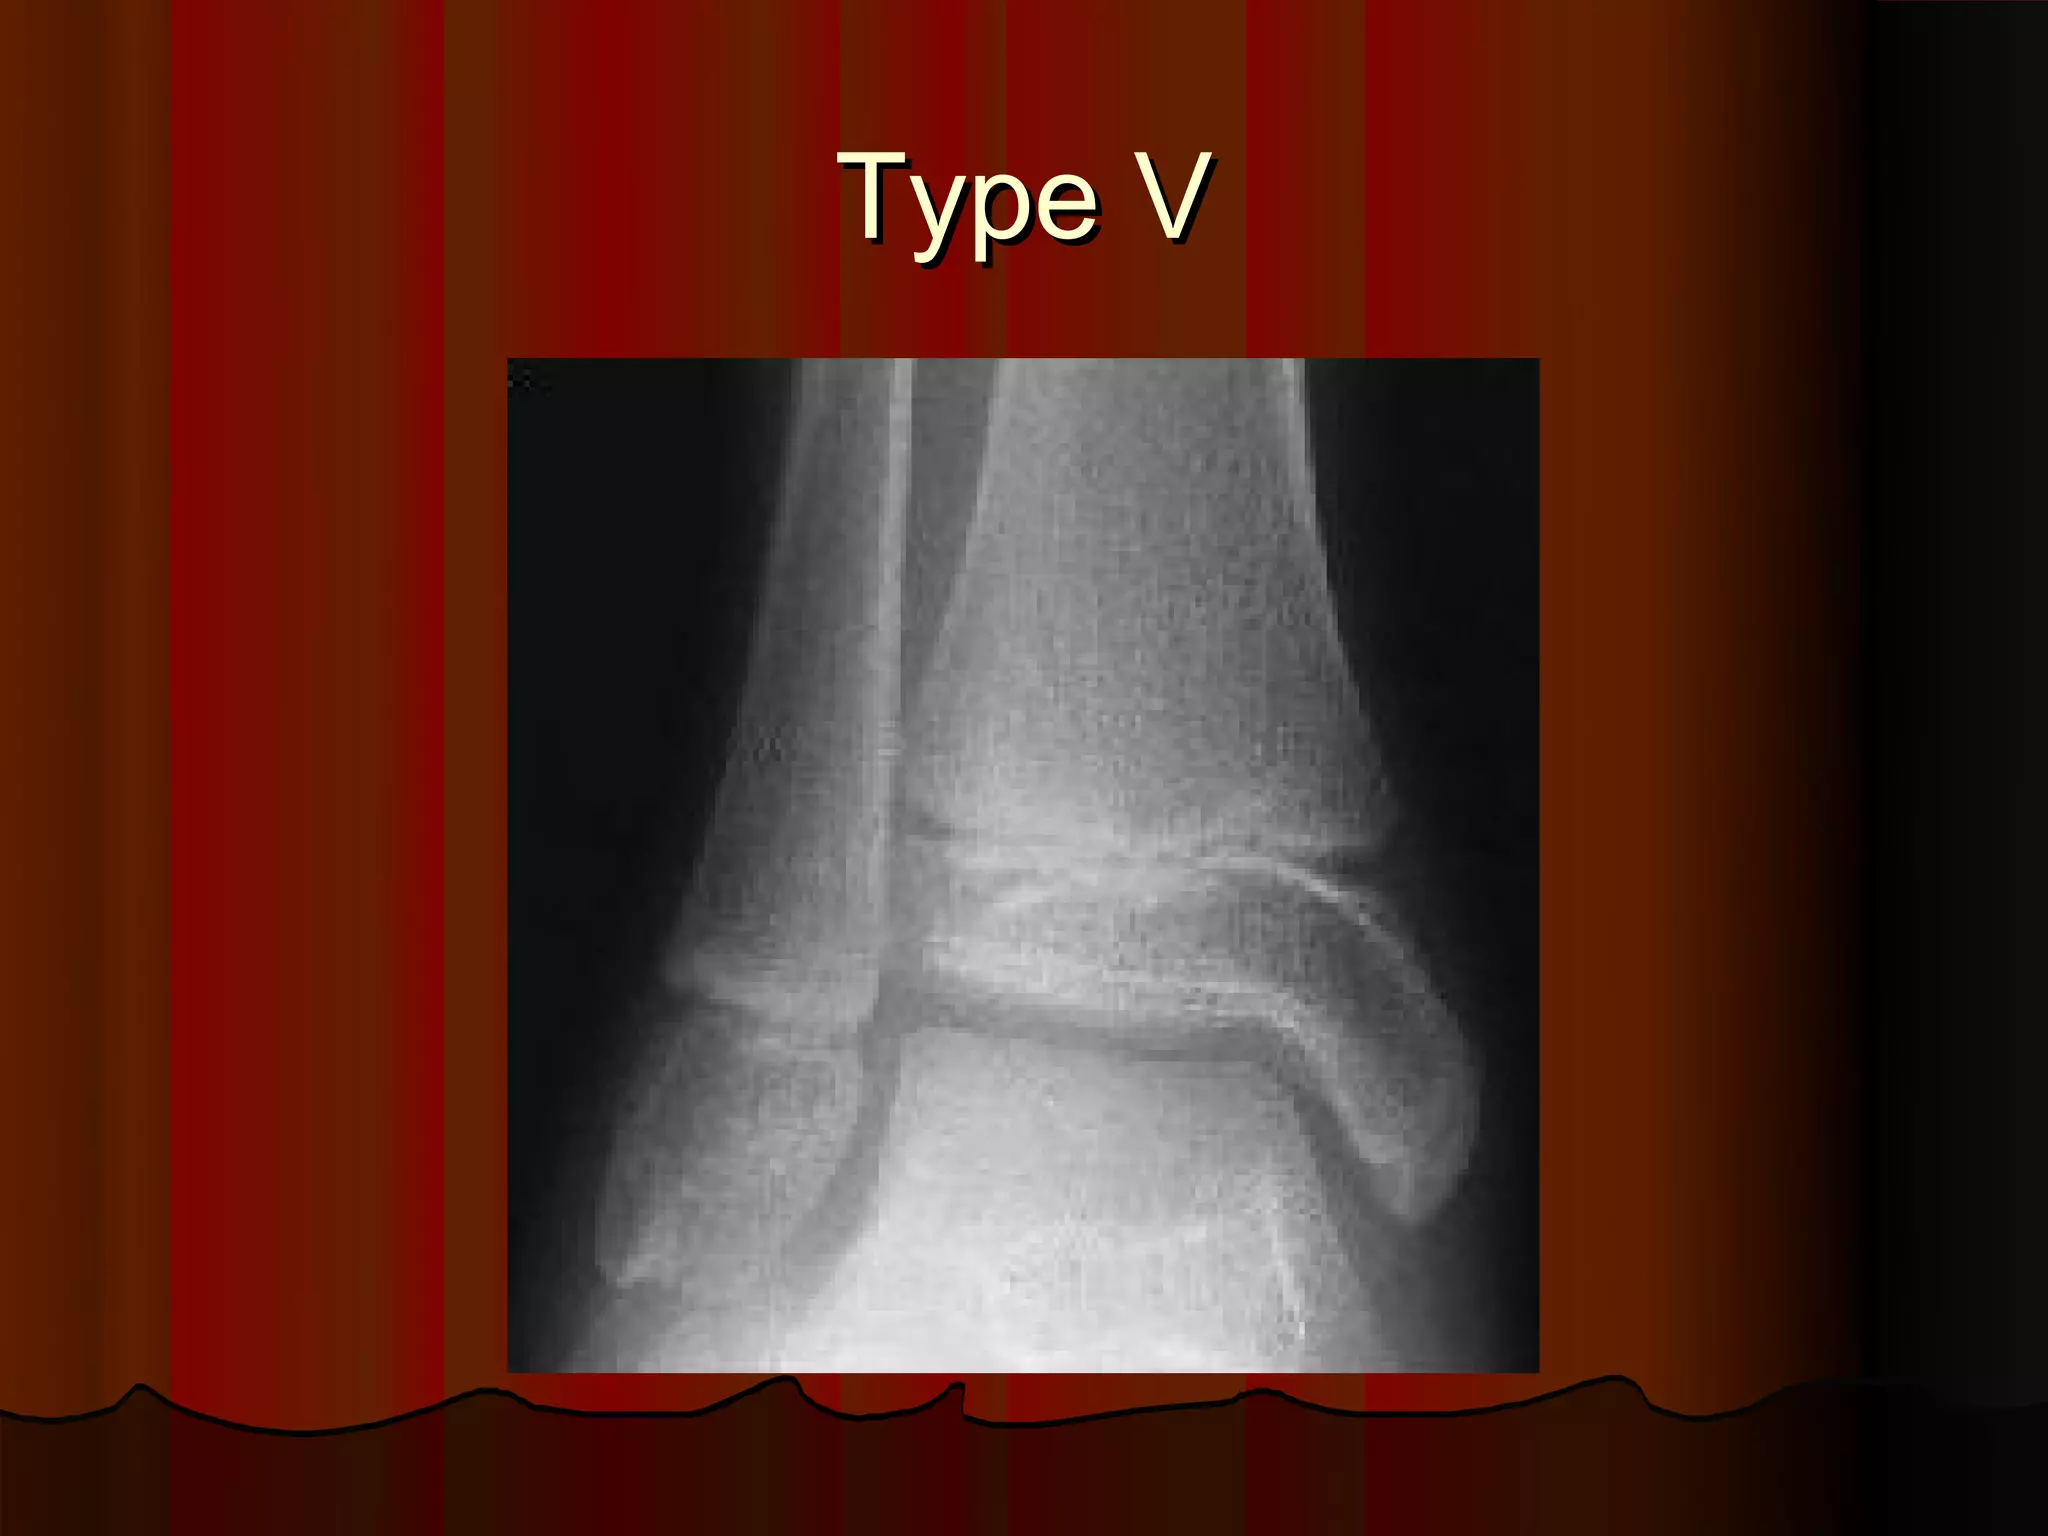

Description of Salter-Harris Type V injury.